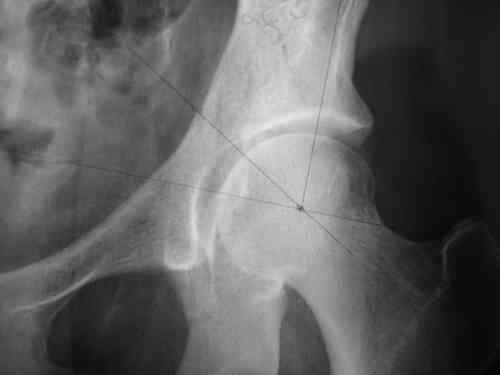

Маленькая иллюстрация (около 5 лет после травмы). Результат плохой - укорочение, хромота, периодически боли в спине, но больной отказывается от операции, видимо, не так все трагично.